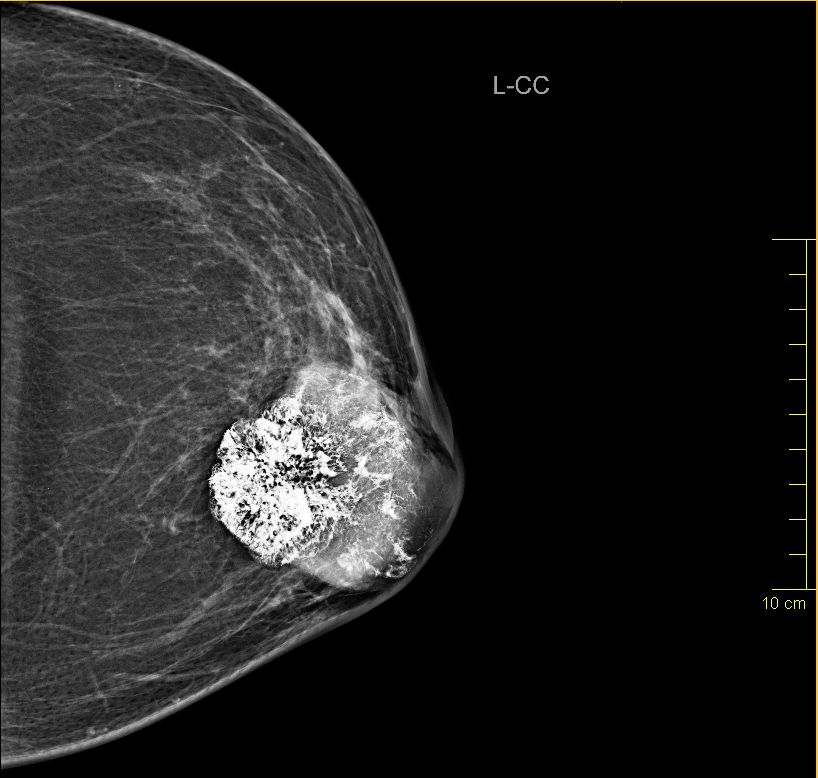

| Fall | 72-jährige Frau, bei der vor 5 Jahren ein gutartiger Tumor diagnostiziert wurde. Vor 8 Monaten war der Tumor auf 4cm angewachsen. Die Exzision wurde empfohlen. Jetzt war der Tumor 66 mm groß, sehr hart und teilweise verkalkt. | |||

| vor OP | Mammographie links MLO.![]() |